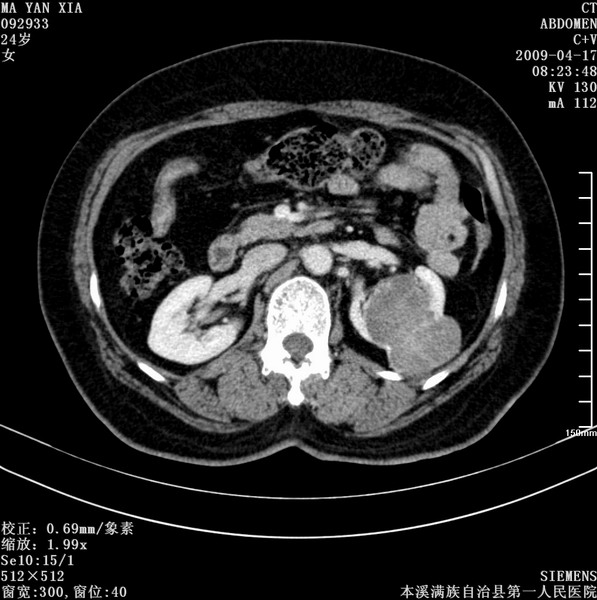

标题: CT19443:肾脏肿瘤两个区强化不一样。 [打印本页]

标题: CT19443:肾脏肿瘤两个区强化不一样。

女,51岁,体检时发现肾脏占位,建议ct增强。无任何自觉症状。

典型的不均匀强化,左肾癌

首先考虑肾癌,但如果术后病理是血管平滑肌脂肪瘤也不意外.